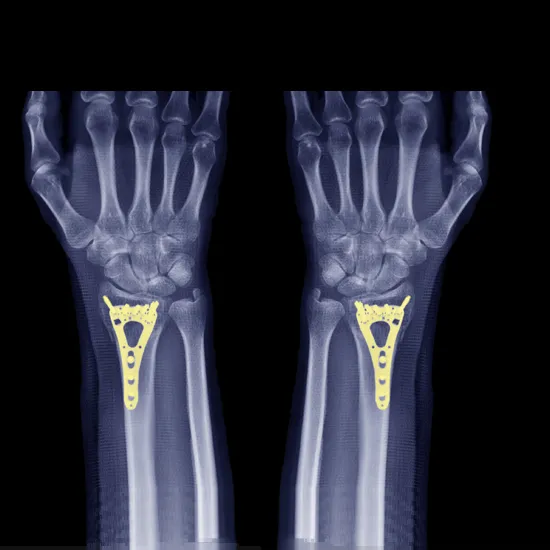

NCCT Right Forearm is a plain scan to visualize the bones in the forearm including the wrist, radius, ulna, forearm, and their surrounding soft tissues of the right side.

• Bone fracture

• To diagnose bone alignment